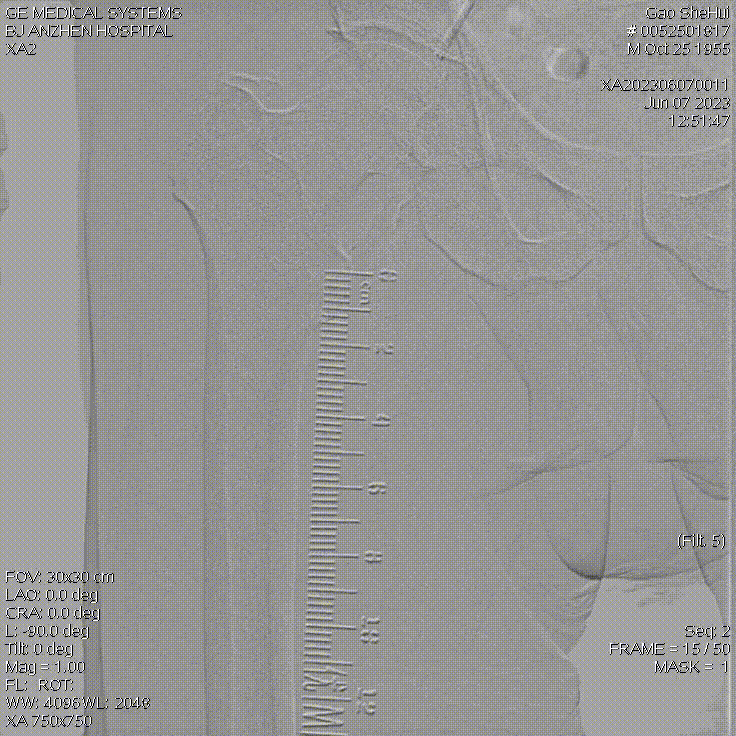

腘动脉、胫腓干的短段闭塞

★ 巧克力球囊

股浅动脉、

腘动脉与胫腓干病变

ELUVIA™ 6-120mm,6-80mm用于股浅

Chocolate 4-150mm, Sterling™ 4-20mm,

DCB 4-150mm